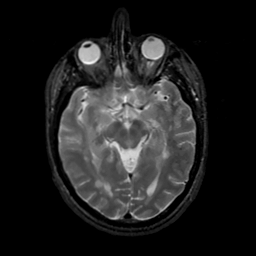

MR Study #7, March 24, 1991 -- Slice #21